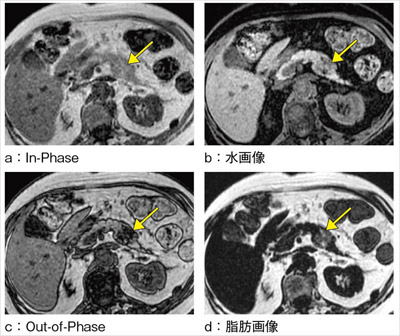

1. 診断のポイント|大腸癌肝転移の画像診断のUP to Date|GI-pedia|消化器癌治療の広場 GI cancer-net, 膵癌、EOB-MRIによる肝転移検索の重要性 | Search Radiology | 医療関係者向け情報,

膵癌、EOB-MRIによる肝転移検索の重要性 | Search Radiology | 医療関係者向け情報, 肝臓MRIにおける最新技術-技術解説 - GEヘルスケア・ジャパン株式会社 - inNavi Suite,